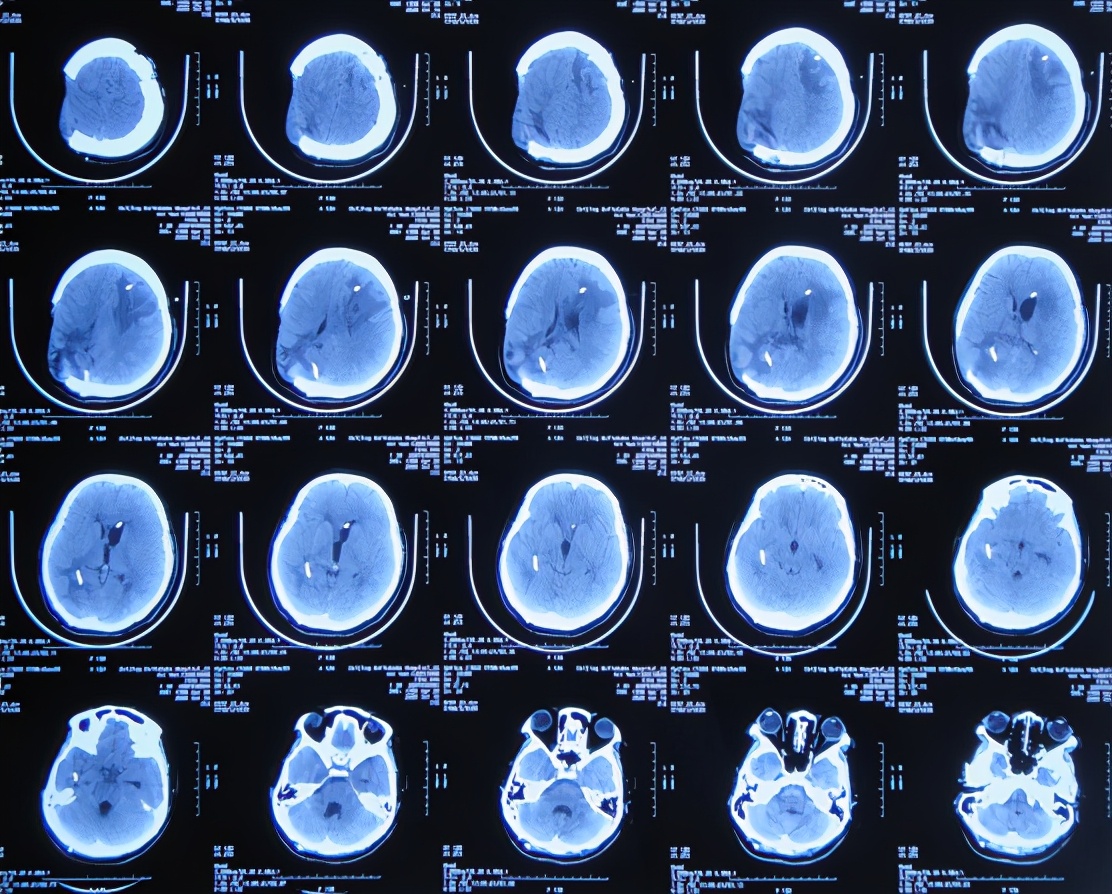

开颅术后次日即2020年4月3日,意识恢复,可简单言语,但左侧肢体偏瘫,仅可在床面平移,伴发热体温最高39.0℃;复查头颅CT示开颅术后去骨瓣状态,出血有减少,引流术后状态( 图-2 )。

图-2: 2020年4月3日头颅CT

开颅术后第3天即2020年4月5日,因出血明显减少,拔除了脑室外引流管( 图-3 )。

图-3: 2020年4月5日头颅CT